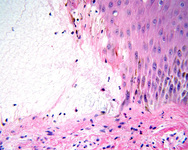

Penfigoide bolhoso

Rede de fibrinas presente na cavidade da vesícula, enquanto o infiltrado dérmico contém muitos eosinófilos

Do acervo da Dra. Vesna Petronic-Rosic